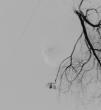

La ecografía Doppler muestra un aumento de la vascularización en la base del cuerpo cavernoso izquierdo (fig. 1). En la arteriografía, se observa la laceración tanto de la arteria peneana izquierda, como de una rama de la arteria obturadora del mismo lado (fig. 2).